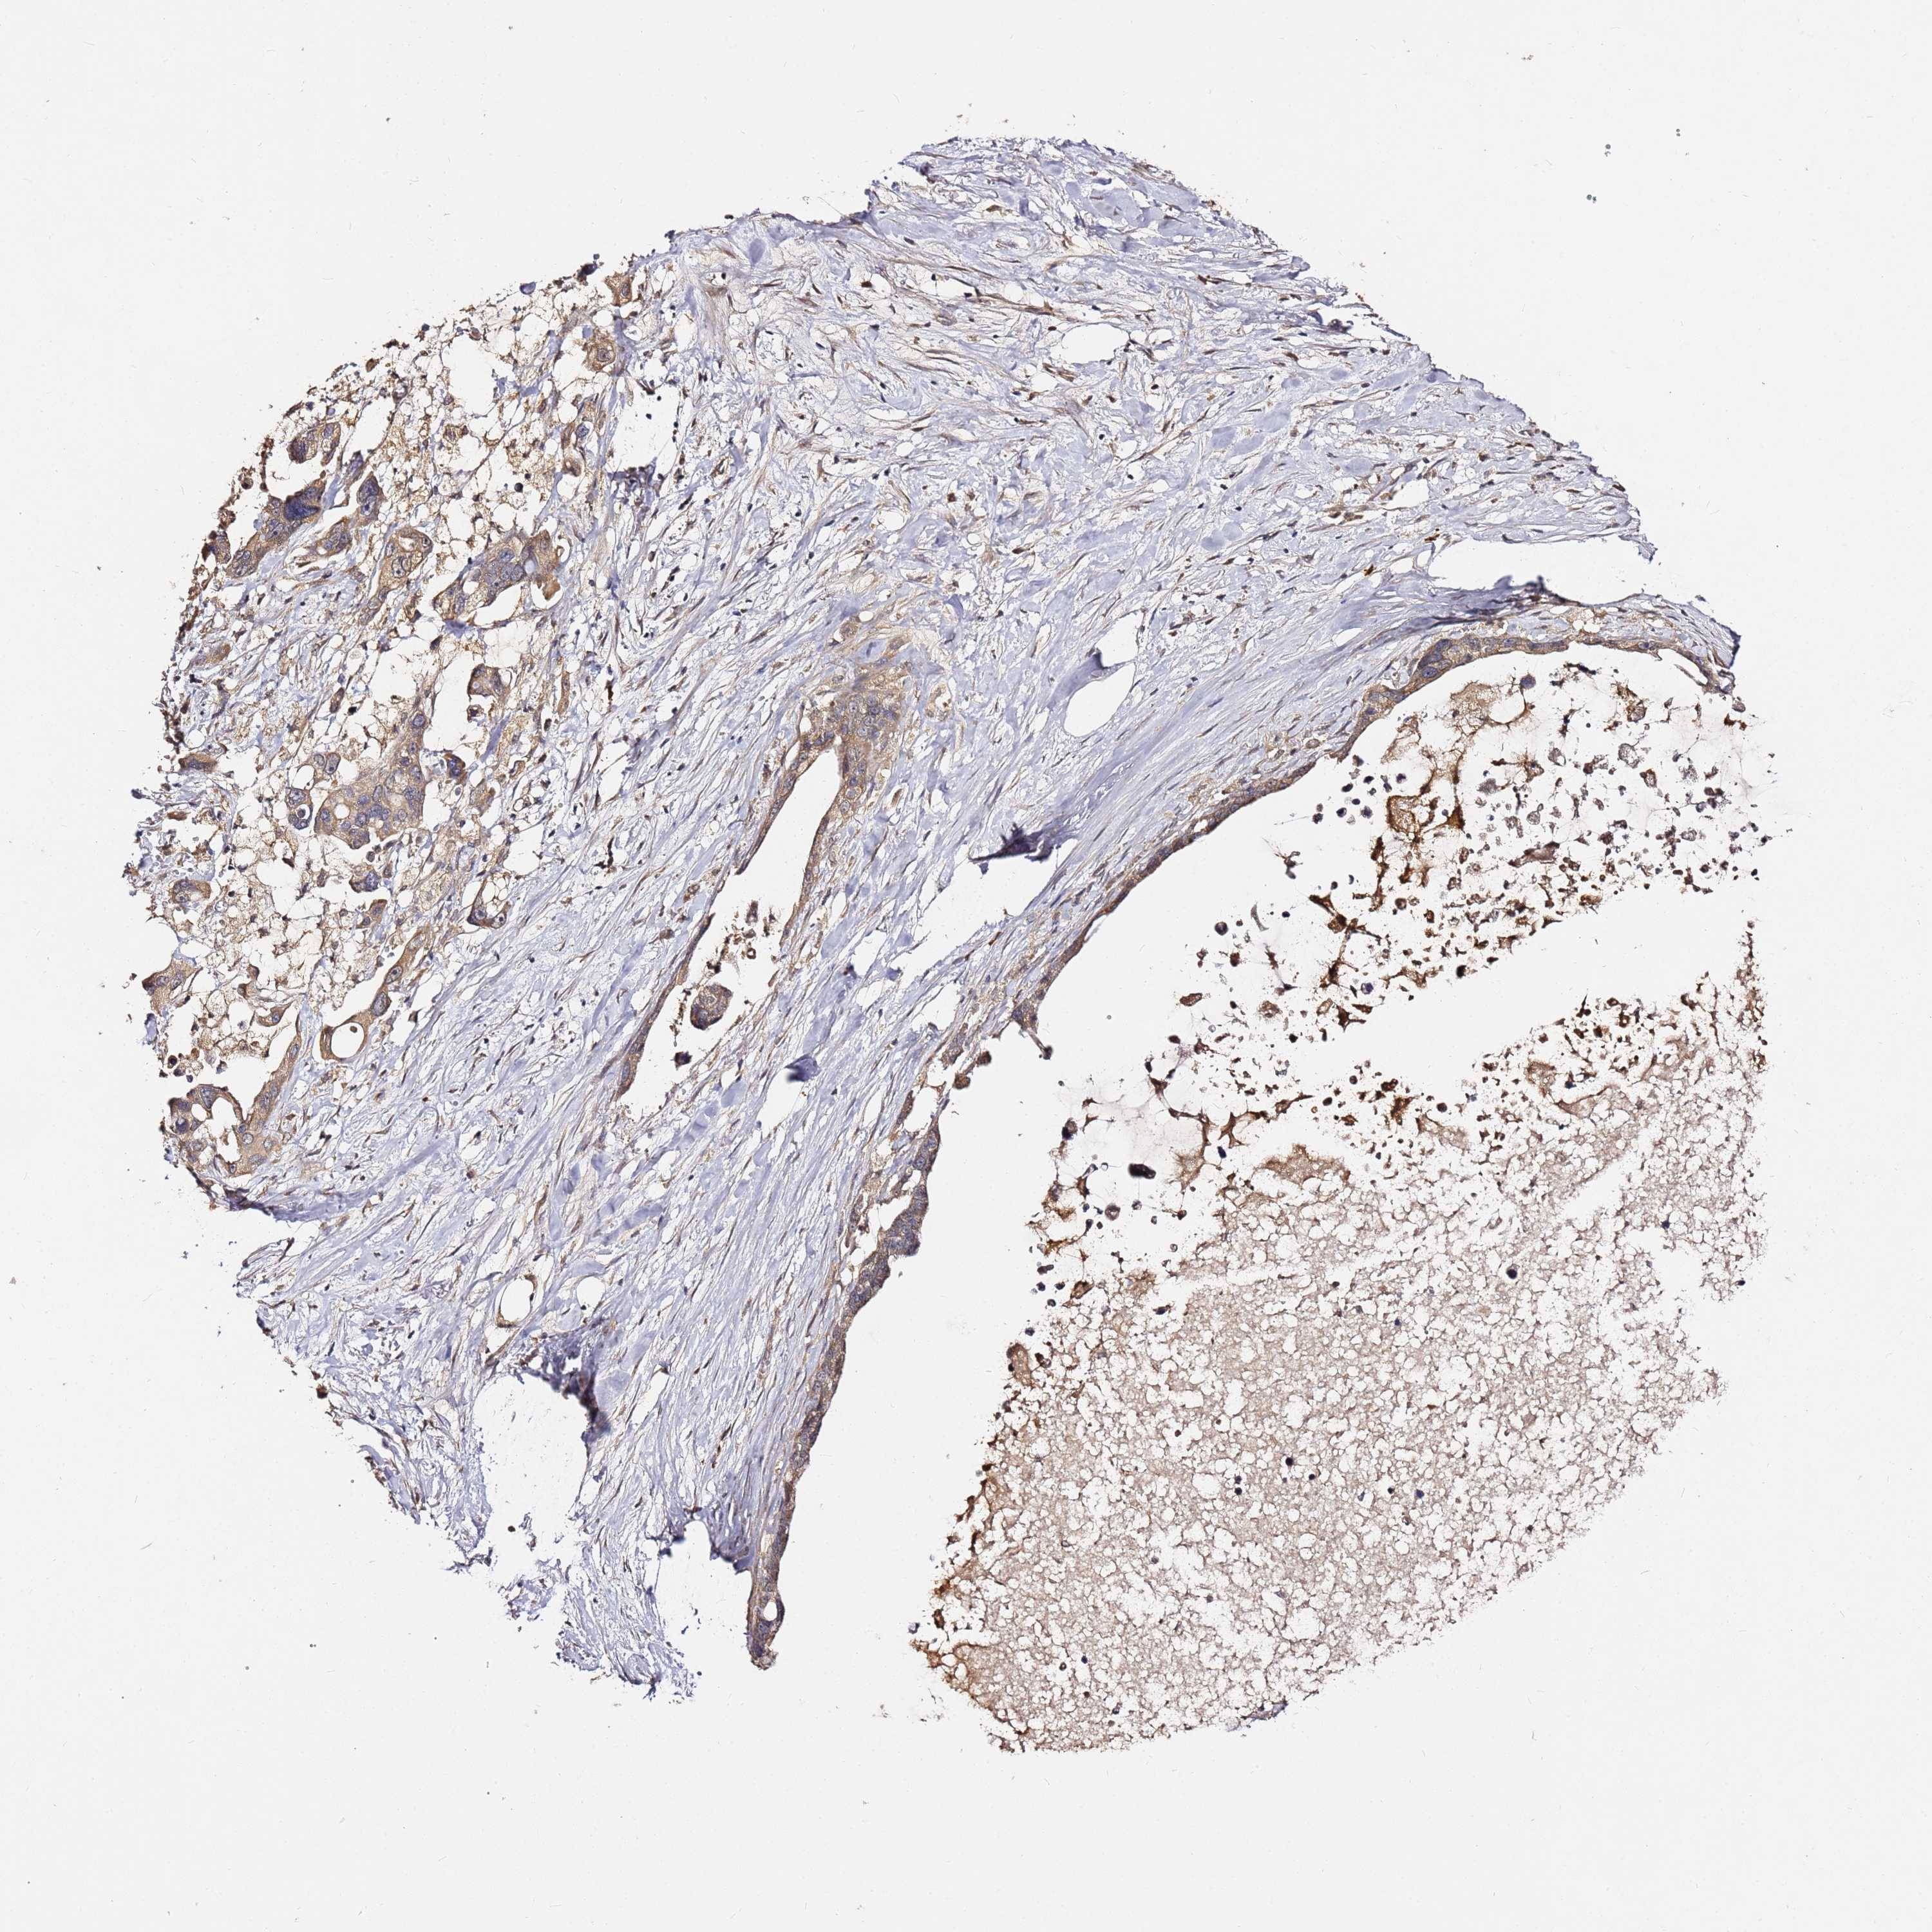

PANCREATIC CANCER - Protein expressioni

A mouse-over function shows sample information and annotation data. Click on an image to view it in a full screen mode. Samples can be filtered based on level of antibody staining by selecting one or several of the following categories: high, medium, low and not detected. The assay and annotation is described here.

Note that samples used for immunohistochemistry by the Human Protein Atlas do not correspond to samples in the TCGA dataset.

Antibody stainingi

Antibody staining in the annotated cell types in the current human tissue is reported as not detected, low, medium, or high, based on conventional immunohistochemistry profiling in selected tissues. This score is based on the combination of the staining intensity and fraction of stained cells.

Each image is clickable and will lead to virtual microscopy that enables deeper exploration of all samples and also displays staining intensity scores, fraction scores and subcellular localization as well as patient and tissue information for each sample.

Antibody HPA046804

Staining

High

Medium

Low

Not detected

Intensity

Strong

Moderate

Weak

Negative

Quantity

>75%

75%-25%

<25%

None

Location

Nuclear

Cytoplasmic/membranous

Cytoplasmic/membranous,nuclear

Adenocarcinoma, NOS